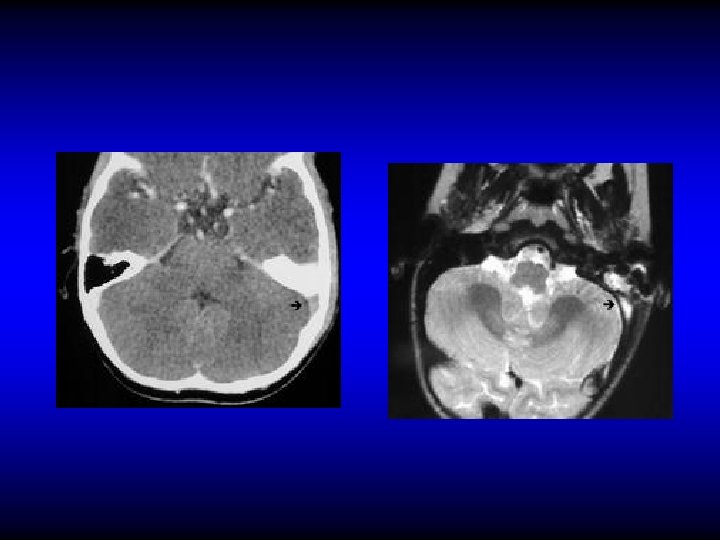

Otogenic brain abscess • 25% of children's and 50% of adult’s brain abscesses are otogenic • Mostly in temporal lobe or cerebellum (2: 1)

Otogenic brain abscess Clinical manifestations • General manifestations: fever, lethargy, headache. • Manifestation of raised IC pressure • Focal manifestations – Temporal: Aphasia, hemianopia, paralysis – Cerebellar: ataxia, vertigo, nystagmus, muscle incoordination

Otogenic brain abscess Diagnosis • CT • MRI

CT

MRI

Otogenic brain abscess Treatment • Repeated aspiration or Excision • IV antibiotics and myringotomy if due to AOM • Mastoid surgery if due to CSOM